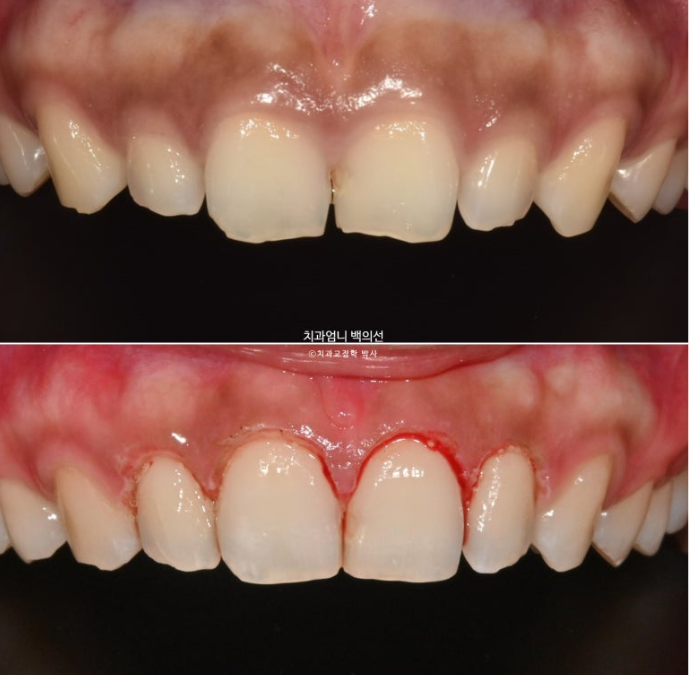

중간에 잇몸성형도 했습니다. 치아를 과도하게 덮고 있는 잇몸을 걷어내는 과정입니다.

24년 9월부터 25년 1월까지, 5개월간 14개 추가장치를 모두 낀 후 모습입니다.

총 치료기간은 10개월 입니다.

25.01

길이가 짧아 답답해보이던 앞니가 잇몸성형으로 비율이 좋아지며 보기에 시원해졌습니다.

이제 전후 비교 보겠습니다.

24.03~25.01

과개교합의 확실한 개선

거미스마일은 많이 개선이 되었습니다.

앞니가 뒤로 쓰러져 있던 옥니도 상당히 개선되었습니다.

10개월의 치료기간 동안 치근흡수는 없으며 치근평행도는 양호합니다.

아래앞니과 위 앞니의 상당량의 함입이 눈에 띕니다. 위아래 앞니가 2mm씩 함입되었습니다.

덕분에 입술은 처음보다 좀 더 편하게 다물리게 되었습니다.